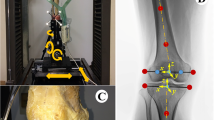

Insert movement and tibiofemoral position were measured by an ultrasonic tracking system (CMS 100®, Zebris GmbH, Isny, Germany), consisting of triplet markers (speakers) forming a plane for each object tracked, and a receiver unit with four microphones. The delay of the received ultrasonic signals between the microphones determined the marker position relative to the receiver unit. Each triplet marker was custom-mounted onto a PVC backing plate, forming an equilateral triangle with a base of 50 mm. One marker triangle was attached to the tibial base plate with its plane visually aligned perpendicular to the base plate horizontal plane. A second triangle was attached to the mobile bearing insert, perpendicular to the horizontal plane of the undersurface of the insert. The third triangle was fixed to the femur with unicortical screws parallel to the long axis of the femur. A distance of 1,000 mm between markers and receiver unit provided measurement of the triangle position at an accuracy of ± 0.1 mm and ±0.1° at a frequency of 10 Hz and a reproducibility of ± 0.005 mm (± 0.005°). Custom motion analysis software based on Excel® (Microsoft, USA) transformed the raw data into the anteroposterior positional coordinates of the insert center and the center of the femur relative to the center of the tibial base plate. The results were plotted as a function of flexion angle.

The specimens were mounted into a specially designed knee simulator in which isokinetic flexion–extension moments are simulated (Fig. 1). The knee specimens were oriented with the femur fixed horizontally and the patella facing downwards. The tibia was attached to the simulator at mid-length by means of a linear-rotational bearing which permits axial sliding and turning of the tibia. The bearing in turn was attached to a swing-arm, which allows varus–valgus rotation. The resulting arrangement gives complete freedom of motion of the joint, with the exception of flexion–extension, which is determined by the position of the swing arm. The swing arm was equipped with a strain gauge based load-measuring device which allows the torsional moment applied to the tibia to be monitored continuously. Movement of the tibia was generated by the coordinated activation of three hydraulic cylinders, one to simulate quadriceps muscle force, one to simulate a proprioreceptive co-contraction of the hamstring muscles and the third to apply an external flexion moment. A specially constructed tendon clamp, which allowed application of loads up to 2,000 N, was used to attach the quadriceps tendon and the hamstrings tendons to the hydraulic cylinder with a steel cable (Fig. 1).

Quadriceps load was measured with an accuracy of ± 0.1 N and a reproducibility of ± 0.005 N using a load cell (Hottinger Baldwin Messtechnik GmbH, Darmstadt, Germany) attached between the tendon clamp and the quadriceps cylinder. Knee flexion degree was measured using a voltage goniometer attached to the tibial swing arm with a frequency of 10 Hz and an accuracy of ± 0.05° and a reproducibility of ± 0.001°.